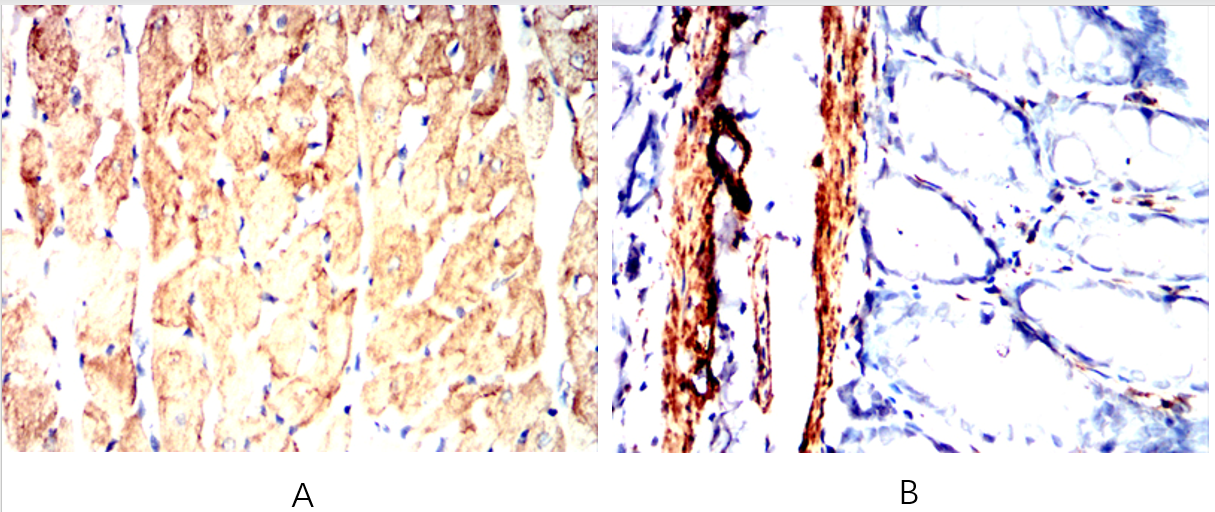

Immunohistochemical analysis of paraffin-embedded Mouse Heart(A) Mouse colon(B) using Desmin mouse mAb with DAB staining.

Immunohistochemical analysis of paraffin-embedded Rat Heart(A) Rat colon(B) using Desmin mouse mAb with DAB staining.

Immunohistochemical analysis of paraffin-embedded Rabbit Heart(A) Rabbit rectum(B) using Desmin mouse mAb with DAB staining.